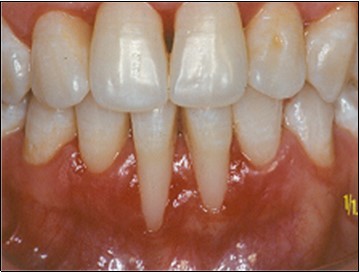

The patient under hard emotional stress that associated with bacterial plaque promoted ANUG with necrosis of alveolar bone and marginal gingival soft tissue in 31 and 41 (Figure 1). The patient was free of systemic disease and was not currently receiving any medication. Initial therapy was carried out using Er-YAG laser, to promote scaling and root planning and oral hygiene instruction. After initial therapy (Figure 2) the surgical method employed consists of the following steps as described by Langer and Langer5.